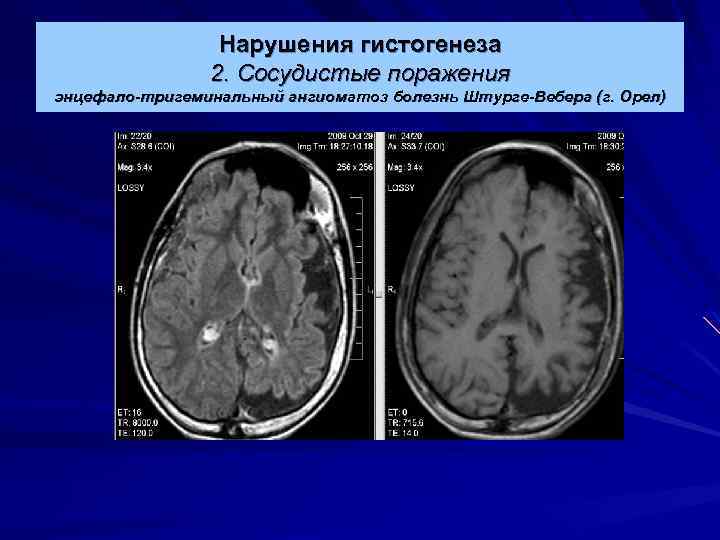

Нарушения гистогенеза 2. Сосудистые поражения энцефало-тригеминальный ангиоматоз болезнь Штурге-Вебера Ребенок 12 лет с эпилепсией и ангиомой на левой половине лица. Обширные участки обызвествления в височно-затылочной области слева.

Нарушения гистогенеза 2. Сосудистые поражения энцефало-тригеминальный ангиоматоз болезнь Штурге-Вебера (г. Орел)